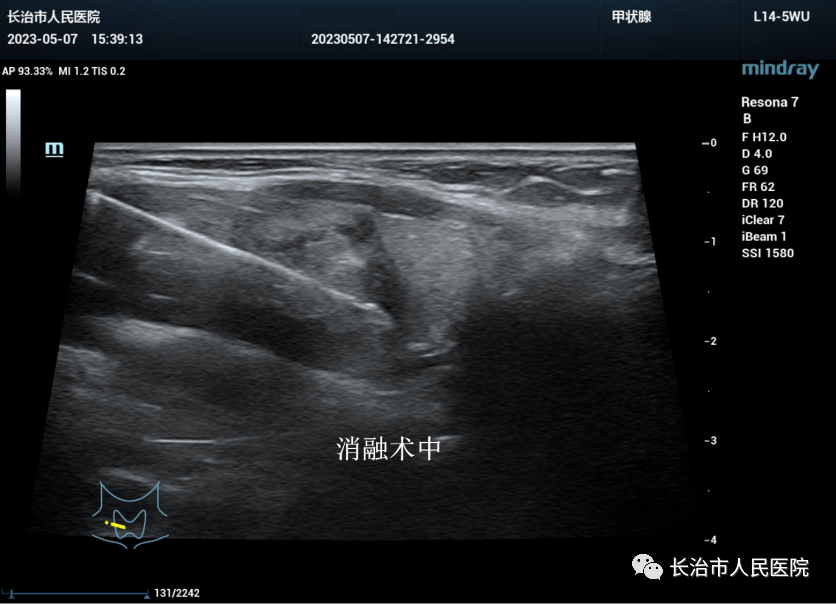

近年来,超声医学技术发展迅猛,尤其是介入超声的发展,迎来了超声从诊断到治疗的里程碑。介入超声以其针过无痕、精准微创等优势获得了临床及患者的认可。10cm大小的肝囊肿,16cm大小的肾囊肿,3cm大小的甲状腺良性结节,0.8cm大小的甲状腺恶性结节,无论其大小良恶,在崔教授精湛的操作技术下,在一根细针的舞动下,在“超声造影”等超声利器的助攻下,短短几分钟或十几分钟,病灶就被“解决”,患者体表只留下一个几乎看不到的针眼。一个巨大肾囊肿患者,术后当场在我院日间手术室门口蹦跳了几下,眉开眼笑,说感觉身体瞬间轻盈了许多。

肝血管瘤虽然是一种良性的疾病,但直径达8cm的血管瘤也会给患者带来许多烦恼。一个偶然机会,听说我院超声医学科开展的新技术,可以微创解决这个问题,患者在网上搜索、找人打听,并来到科室咨询。科室医生为患者进行了详细的超声检查,评估了手术的可行性,耐心地讲解了超声引导下微创治疗的种种相关事宜。患者得知手术是在国内知名超声专家的指导下操作完成,且不收取任何专家手术费时,终于放下了最后一丝顾虑,决定在我院实施超声引导下微创注药手术。与崔教授多次的探讨,为患者数次的超声检查评估,术中的严谨规范,最终使手术顺利完成。看似云淡风轻的一台小小的介入超声手术,却是“对标一流,严谨规范,医患和谐,同心共铸”的成果。